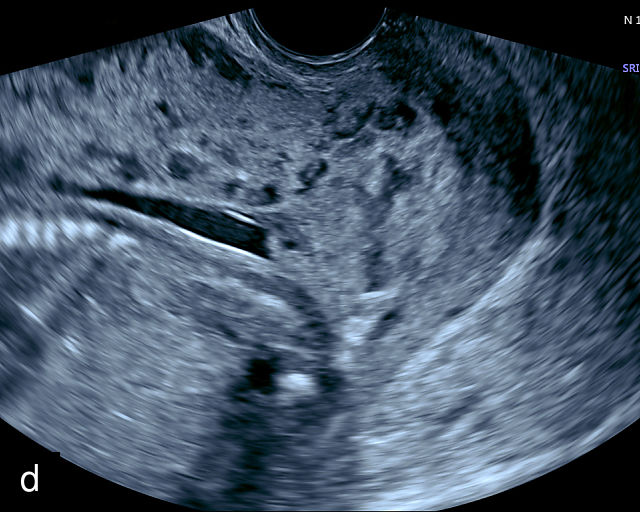

6

Placenta accreta spectrum. (a,b) Sagittal transabdominal grayscale ultrasound of the lower uterus and cervix demonstrating placenta previa accreta, with the placenta (p) containing prominent irregular hypoechoic lacunae. There is absence of the myometrium at the bladder (b) interface (arrows) c, cervix. (c) Sagittal transabdominal color Doppler ultrasound of the lower uterus and cervix demonstrating placenta previa accreta, with increased vascularity of the lower uterus and the myometrial bladder interface. (d) Transvaginal ultrasound of placenta previa accreta showing multiple lacunae involving the cervix with no clear demarcation between the placenta and the cervix. (e) Transvaginal ultrasound of placenta previa accreta showing multiple large irregular lacunae involving the cervix with no clear demarcation between the placenta (p) and the cervix. The placenta has a ‘moth-eaten’ appearance. There is loss of myometrium (arrows). (f) Transvaginal ultrasound of placenta previa accreta without and with color flow Doppler showing multiple large irregular lacunae. The placenta has a ‘moth-eaten’ appearance. There is hypervascularity of the myometrial interface. (g) Transvaginal ultrasound of placenta previa accreta showing multiple lacunae involving the cervix with no clear demarcation between the placenta and the cervix. (h) Transvaginal ultrasound of placenta previa accreta with color flow Doppler showing hypervascularity of the myometrial interface and irregularity of the bladder wall. b, bladder; p, placenta. (i) Transabdominal grayscale ultrasound of cesarean scar pregnancy. The uterine fundus (f) is empty (arrowhead). The gestational sac (arrow) is located in the lower uterus, anterior to the uterine canal, and lies above the cervix (c). b, bladder. (j) Transvaginal grayscale ultrasound image of cesarean scar pregnancy showing the empty fundus (f) and the normal cervix (c). The gestational sac lies below the fundus, above the cervix and anterior to the uterine cavity. (k) Transvaginal grayscale ultrasound image of cesarean scar pregnancy showing the empty cavity (arrowheads) of the uterine fundus (f), and the normal cervix (c). The gestational sac lies below the fundus, above the cervix and anterior to the uterine cavity (arrow).

Several characteristic sonographic findings are associated with PAS.90,95,96,97 These include placental lacunae, which appear as hypoechoic, irregular spaces within the placenta with high-velocity turbulent flow on color Doppler.16,50 Other features include obliteration of the retroplacental clear space, thinning of the myometrium in the lower uterine segment, irregularity and hypervascularity of the myometrial–bladder interface, and placental bulging into the bladder (Figure 6a–h).90,96,98,99